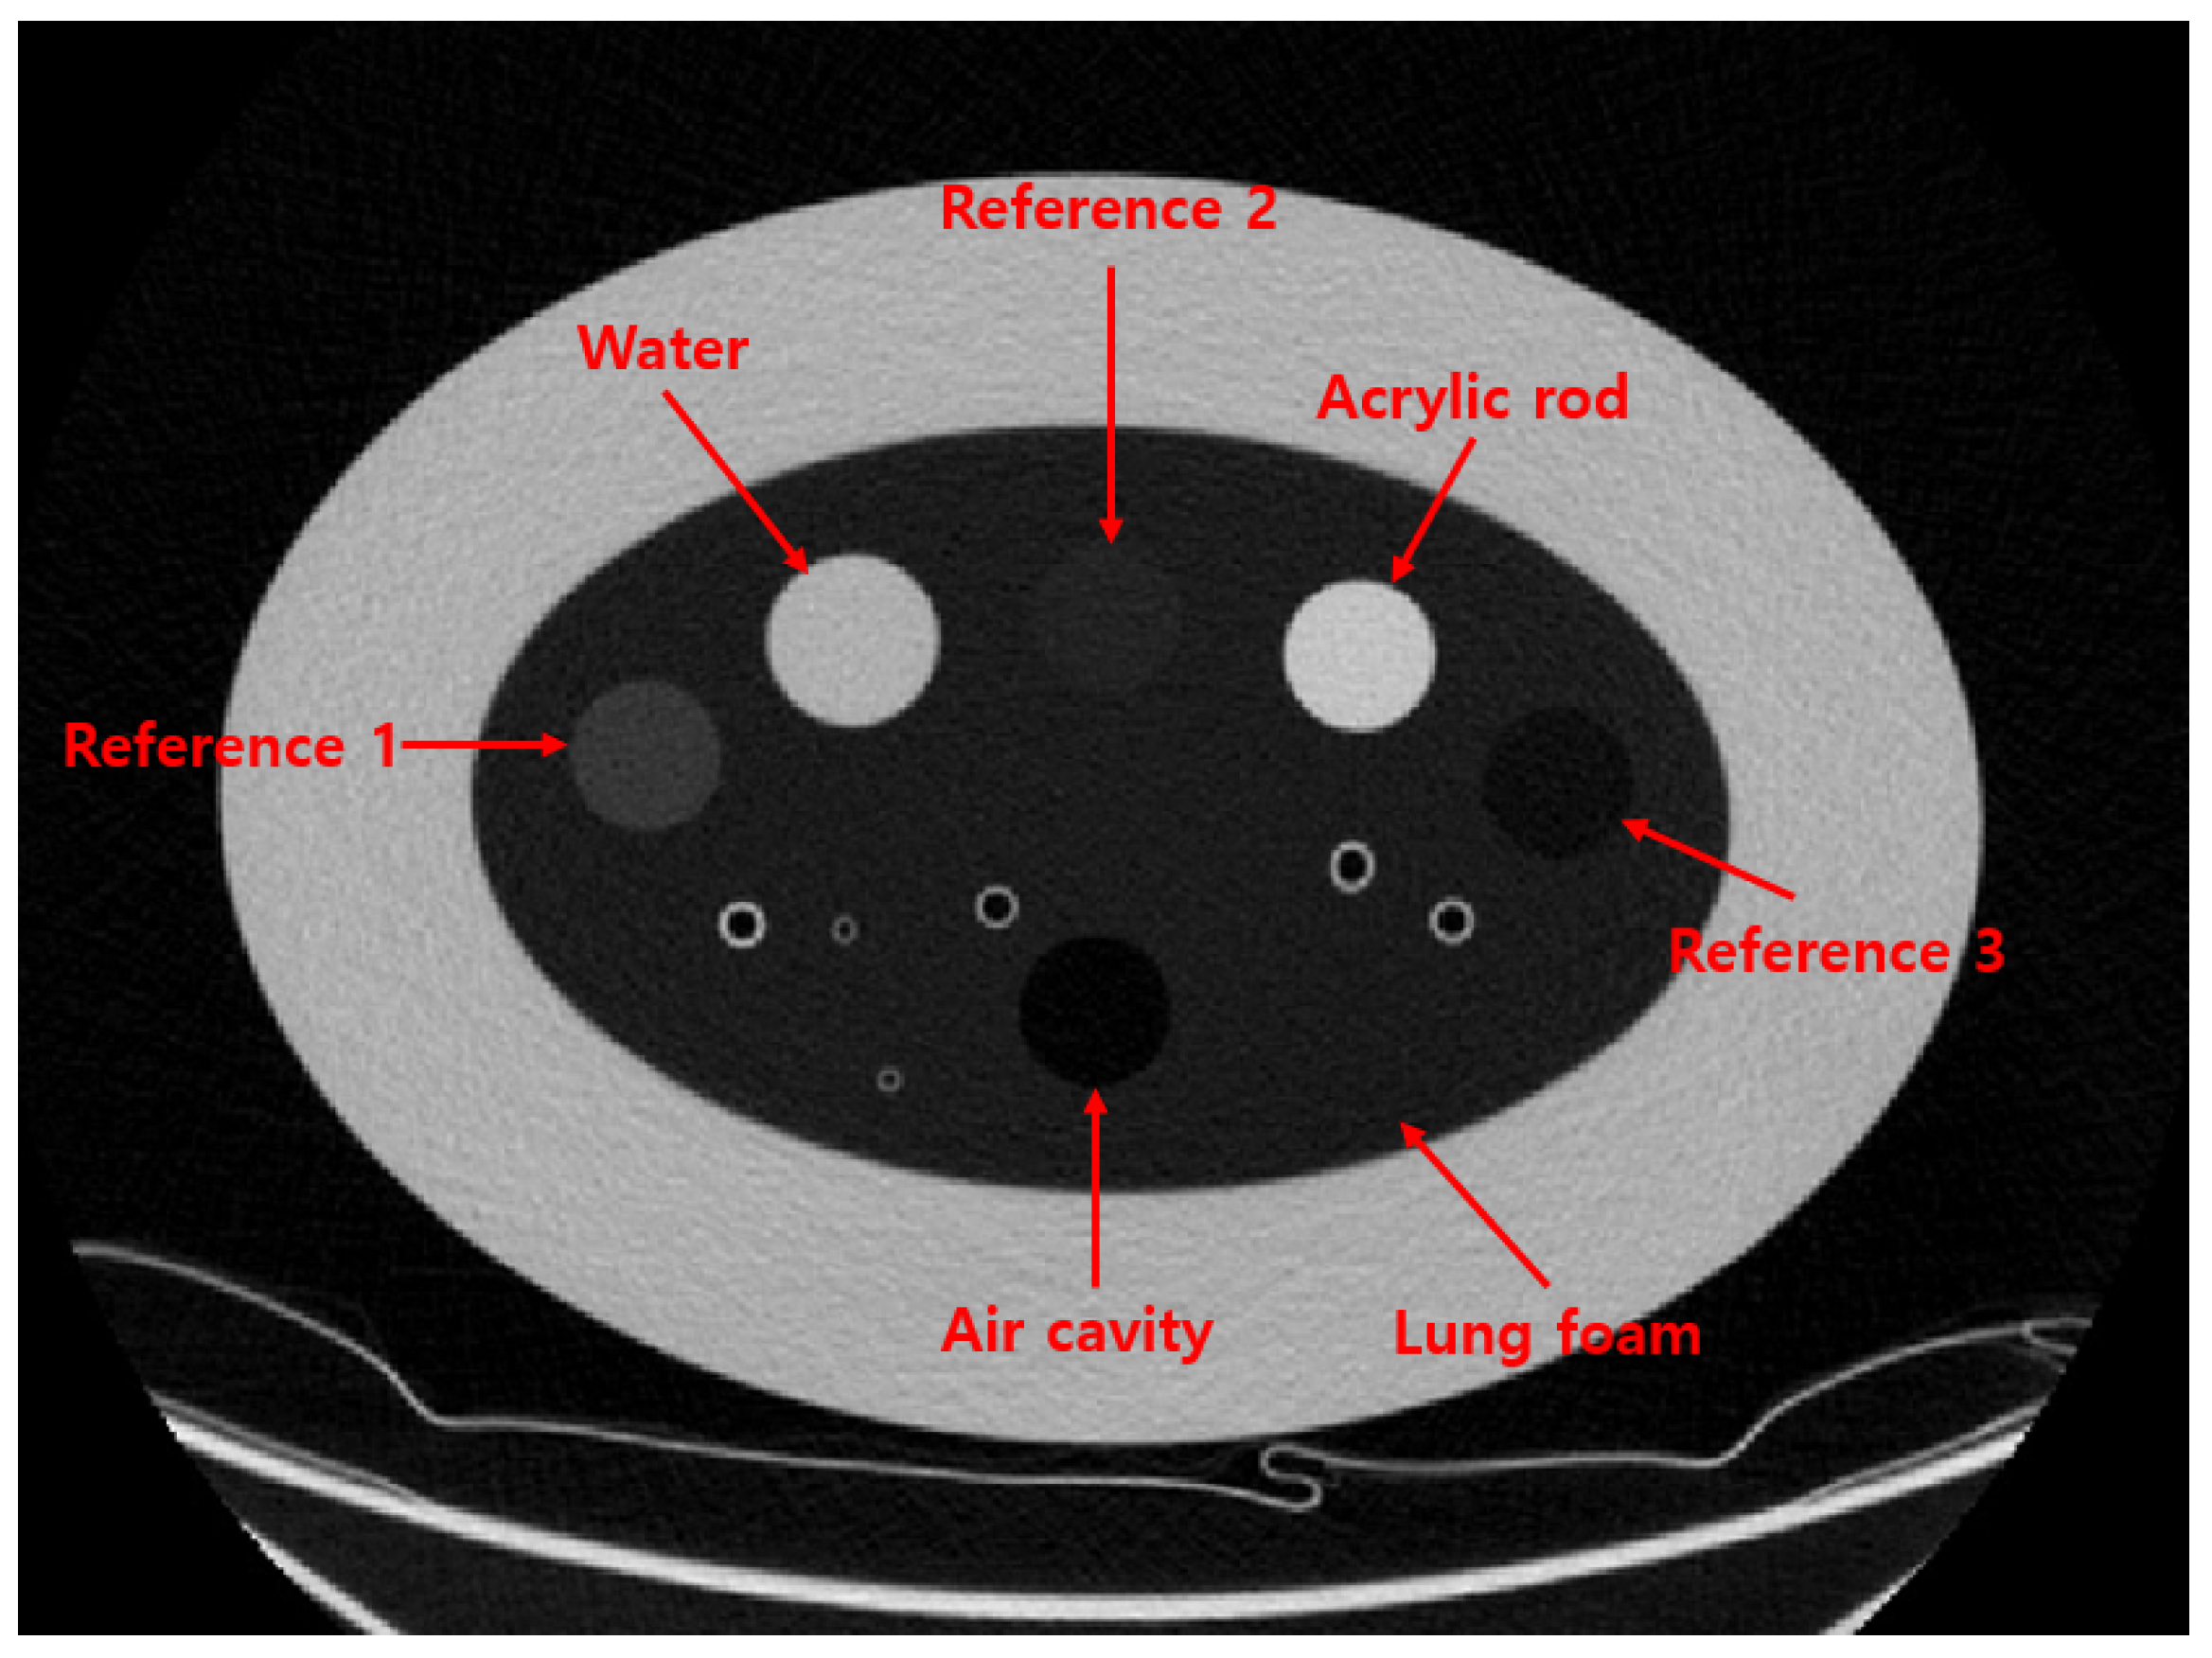

To evaluate the performance of the proposed method, we used the COPD gene2 phantom (CTP698; The Phantom Laboratory, Schenectady, NY, USA), as shown in Figure 2. The phantom comprises air and water sealed in silicone cylinders, an acrylic rod, and three reference foams with different densities. The nominal densities of the reference foams are 64.2 kg/m3, 192.6 kg/m3, and 321.0 kg/m3, respectively [9,10]. These reference foams are surrounded by an oval-shaped lung foam with a measured density of 160.2 kg/m3, corresponding to normal pulmonary parenchyma [10].

All materials in the COPD gene2 phantom are registered with the National Institute of Standards and Technology (NIST) Standard Reference Material (SRM) foam suite [11,12]. Based on the SRM foam suite, the CT numbers of the reference foams are expected to be −700, −820, and −935 HU, respectively, while the lung foam has a CT number of −856 HU. A detailed list of the materials and their corresponding densities and CT numbers in the COPD gene2 phantom is provided in Table 2.

Figure 2. CT image of COPD gene2 phantom.

Table 2. Reference foams of COPD gene2 phantom.

Foam NumberFoamDensity (kg/m3)CT Number (HU)

1Reference 1321.0−700

2Water1000.00

3Reference 2192.6−820

4Acrylic rod1180.0130

5Reference 364.2−935

6Air0−1000

7Lung160.2−835